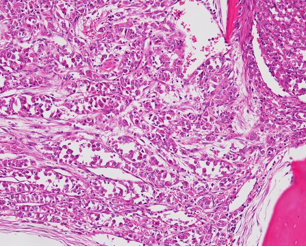

For further identification, we performed 18F-fluorodeoxyglucose position emission (FDG PET-CT), which demonstrated a high FDG uptake in the right kidney and left ilium of this patient with SUVmax values of 8.1 and 4.8, respectively (Figure 2B and Figure 2C). Additional enhanced dynamic CT of the kidney showed no tumor lesions in the right kidney. Meanwhile, the high level of FDG uptake in the right kidney was judged to be the result of urine pool due to the double renal pelvis. Given that needle biopsy did not lead to the confirmation of a histopathological diagnosis, incisional biopsy was performed. Thus, we observed that the tumor was composed of proliferating round-shaped cells with eosinophilic or clear cytoplasm. Via immunohistochemistry, we confirmed that the tumor cells were positive for PAS, but negative for HMB45, S100, and desmin. Moreover, occasional vein tumor embolisms were observed. These findings were suggestive of PEComa (perivascular epithelioid tumor) or ASPS. Additional reverse transcriptase polymerase chain reaction (RT-PCR) using a fresh frozen sample of the biopsy demonstrated the presence of ASPSCR1-TFE3 gene fusion. Therefore, the tumor was diagnosed as ASPS based on the expression of this characteristic fusion gene.

Figure 6: Photomicrograph showing the presence of irregular sheets consisting of round cells and vessels between trabecula. ×200 Hematoxylin-eosin.